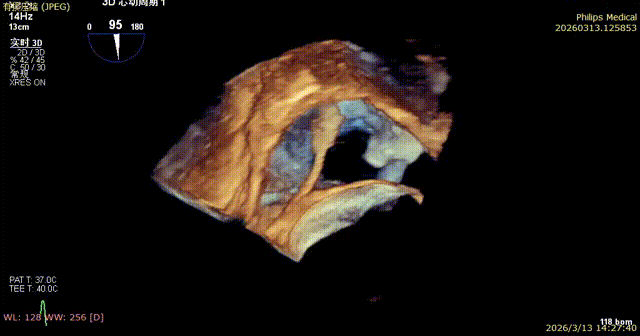

Comparison of Regurgitation Before and After Surgery

Baseline preoperative regurgitation

Postoperative regurgitation baseline

Comparison of Tricuspid Annular Area After Annuloplasty

Preoperative tricuspid annular area: 15.6 cm²

Postoperative tricuspid annular area: 7.68 cm²

Following annuloplasty, leaflet coaptation was improved compared with the preoperative state, and regurgitation was reduced from severe to trivial.